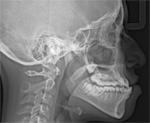

Idiopathic Root Resorption/Orthognathic Surgery Case

Have you ever seen root resorption to this extent? Would you have the same treatment plan as the ortho assigned to this case?

Orthodontic Root Resorption – Update

This course will update the clinician on what is currently known about external apical root resorption. You will learn which patients are the most at risk. You will understand what the etiology is, and what diagnostic and treatment factors must be considered.